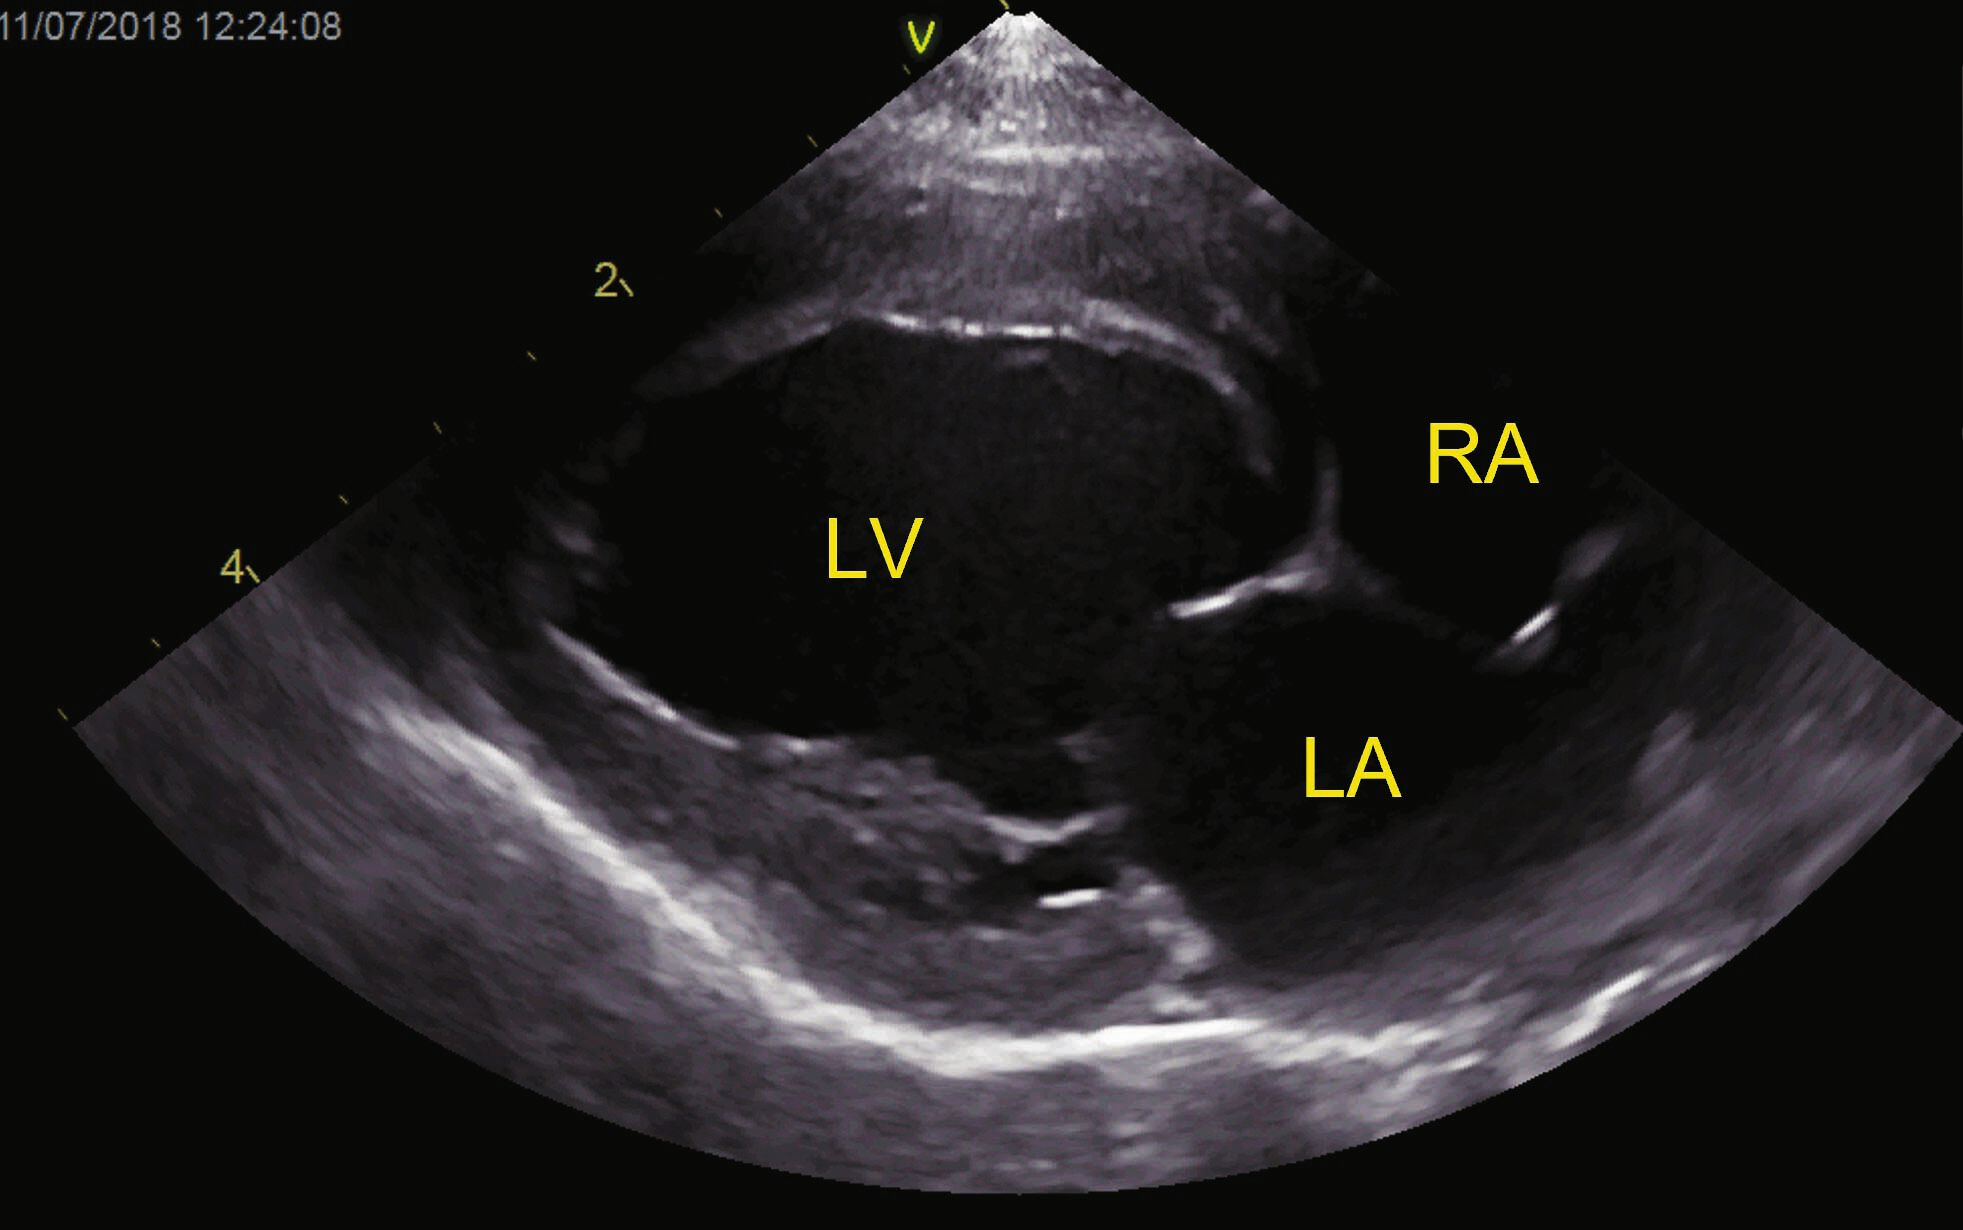

3. La cardiomyopathie non spécifique (anciennement appelée cardiomyopathie atypique) [2]. Ici, les signes échocardiographiques ne sont pas facilement superposables aux autres critères de cardiomyopathie (par exemple, dysfonctionnement systolique et diastolique sans dilatation du VG ou hypertrophie accrue) ; les caractéristiques de plusieurs cardiomyopathies peuvent aussi être associées (Figure 6).

Vue PSD (grand axe, 4 chambres) d’un chat à poil court diagnostiqué avec une cardiomyopathie atypique

Figure 6a. Vue PSD (grand axe, 4 chambres) dun chat poil court diagnostiqu avec une cardiomyopathie atypique. Le chat prsentait un panchement pricardique (PE) et pleural (Pl Eff) avec une ICC. Il y avait une dilatation marque de latrium gauche, associe un dysfonctionnement diastolique. Le ventricule gauche (VG) ntait pas particulirement dilat et lpaisseur de sa paroi se situait dans la fourchette de rfrence, mais la fonction systolique tait altre. Catheryn Partington Joanna Dukes-McEwan